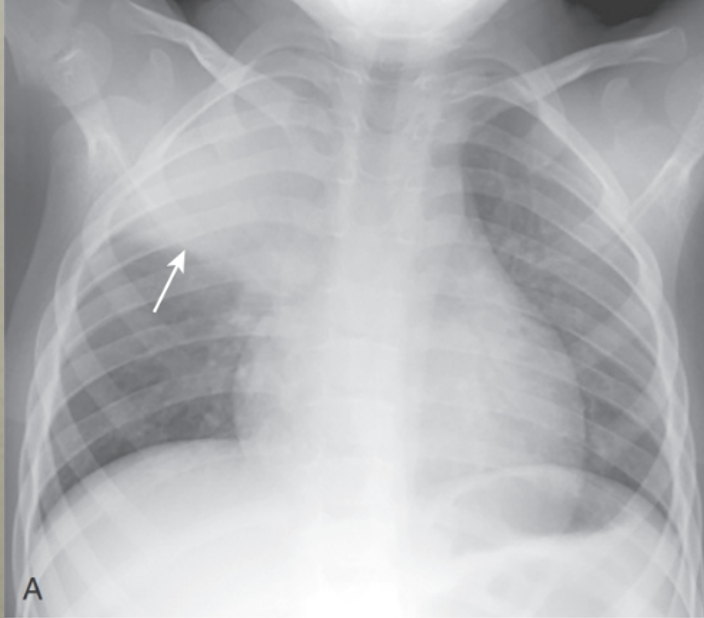

Q

RUL Pneumonia:

* This disease obscures the ascending aortia and produces a sharp margin where it abuts the minor fissure (arrow)